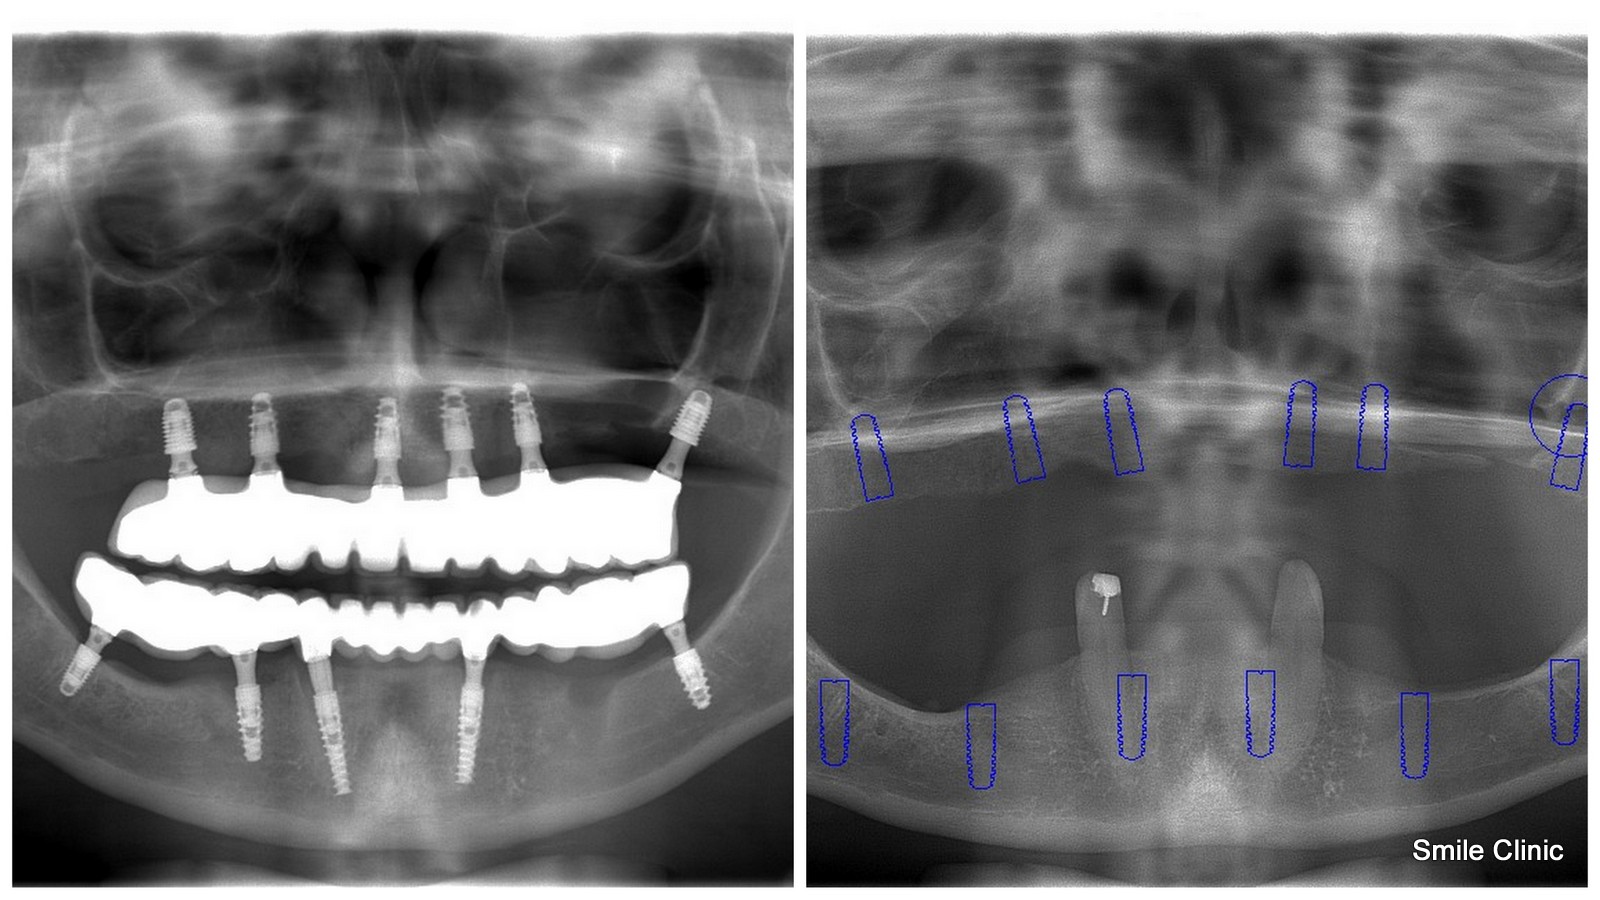

As you can see from the X-ray in this post, this soon-to-be-wed lady had almost no existing teeth whatsoever, and was wearing false teeth dentures. Of course, like most of us, she felt very uncomfortable wearing them.

Dental Holiday in Slovakia offers a same day replacement of the whole upper and lower jaw with a semi-permanent bridge based on dental implants (11 were used in this case to add extra strength support in the thin amount of jawbone available for stable bridge support).